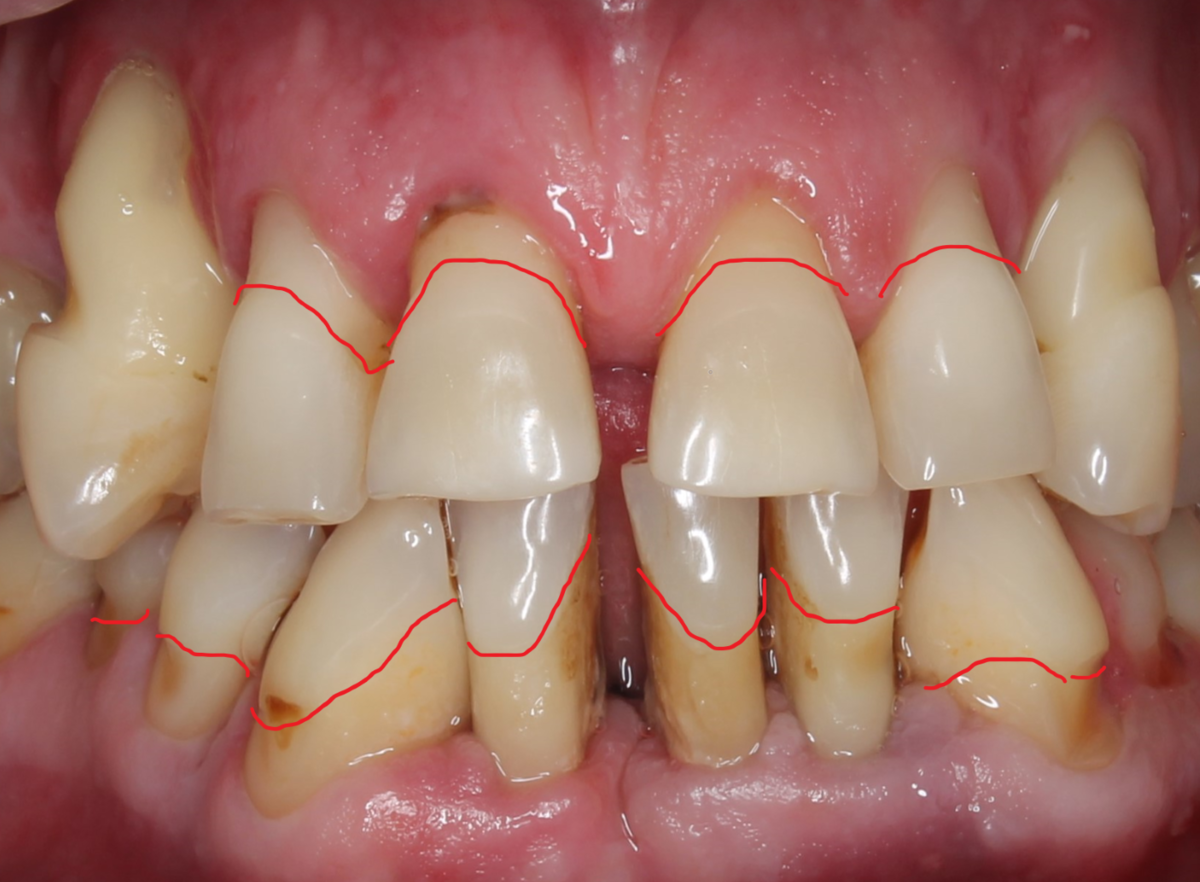

Оголённые корни зубов на верхней челюсти.

Я провела линии, разграничивающие норму и патологию. Об этом случае можно почитать вот тут.

Зуб, упрощённо, состоит из эмали (над десной) и корня, покрытого цементом (под десной). Линия, разделяющая эмаль/корень называется ЦЭС - цементно-эмалевое соединение.

Зато чётко ведь видно, где эмаль а где корень?

А тут прямо таки можно увидеть линию раздела.

Если приглядеться, можно увидеть линию, разделяющую две зоны. Эмаль - светлее, более гладкая и лучше блестит.

Снова - эмаль явно светлее. Чётко видно границу раздела. Межзубные сосочки и кость сохранны - это не пародонтит.